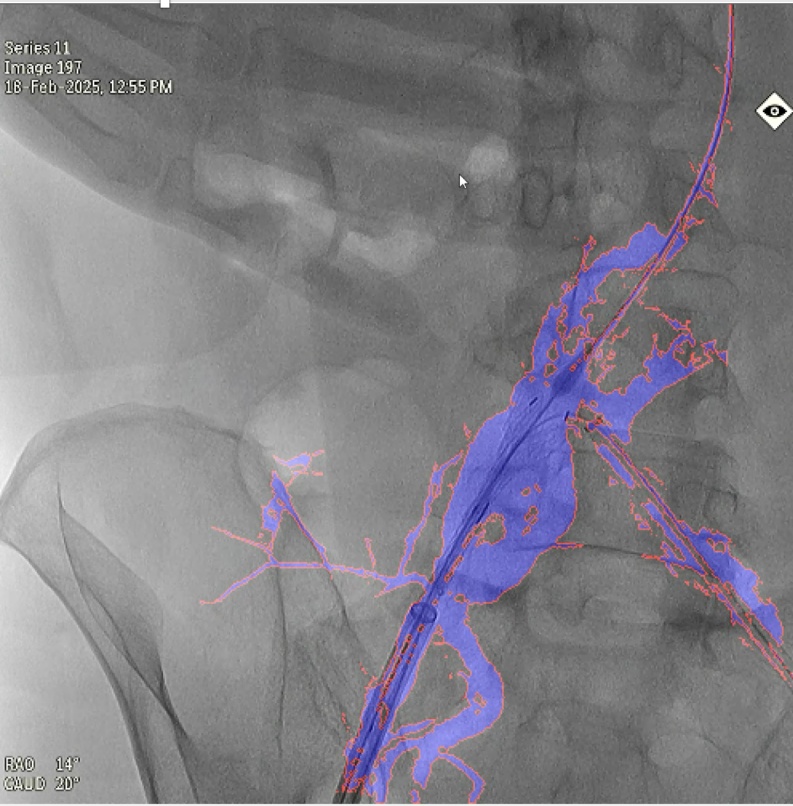

禄韶英教师团队与北京飞燕四海医疗科技公司的工程师联袂谐和,纠合当今开首进的图像分割、及时标注算法,研发出了基于神经网罗、AI深度学习的DSA术中及时导航软件“AngiSight”。该软件杀青了三大技能冲突:在体位固定下达到0.1毫米级血管概括识别的精确导航,床位变动后3-5秒内完成新图像会通的及时反应,以及无需建立硬件升级即可适配各品牌DSA机型的平庸兼容性。运用该系统对52例临床真正病例进行回来性扣问恶果证实,不仅斥责了40%的辐射认知,单次手术精真金不怕火60%造影剂,还使急诊手术时期裁减了35%,为抢救赢得了黄金窗口,同期提升了慢性血管阻塞等疑难病例15%的收效能。

本扣问案例,使用10ml造影剂一次造影,杀青EVAR术中髂内动脉重建,图中蓝色部分为造影炫耀的真正血管,红色边框为图像分割恶果,会通图像的透明度可退换,与真正血管十足贴合,血管、器械的细节齐了了可见。